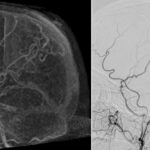

This prospective study compared 4D-CTA and DSA for the detection or arterio-venous shunts and found that CTA was able to replace DSA as the first work-up modality. Article: High sensitivity and specificity of 4D-CTA in the detection of cranial arteriovenous shunts...